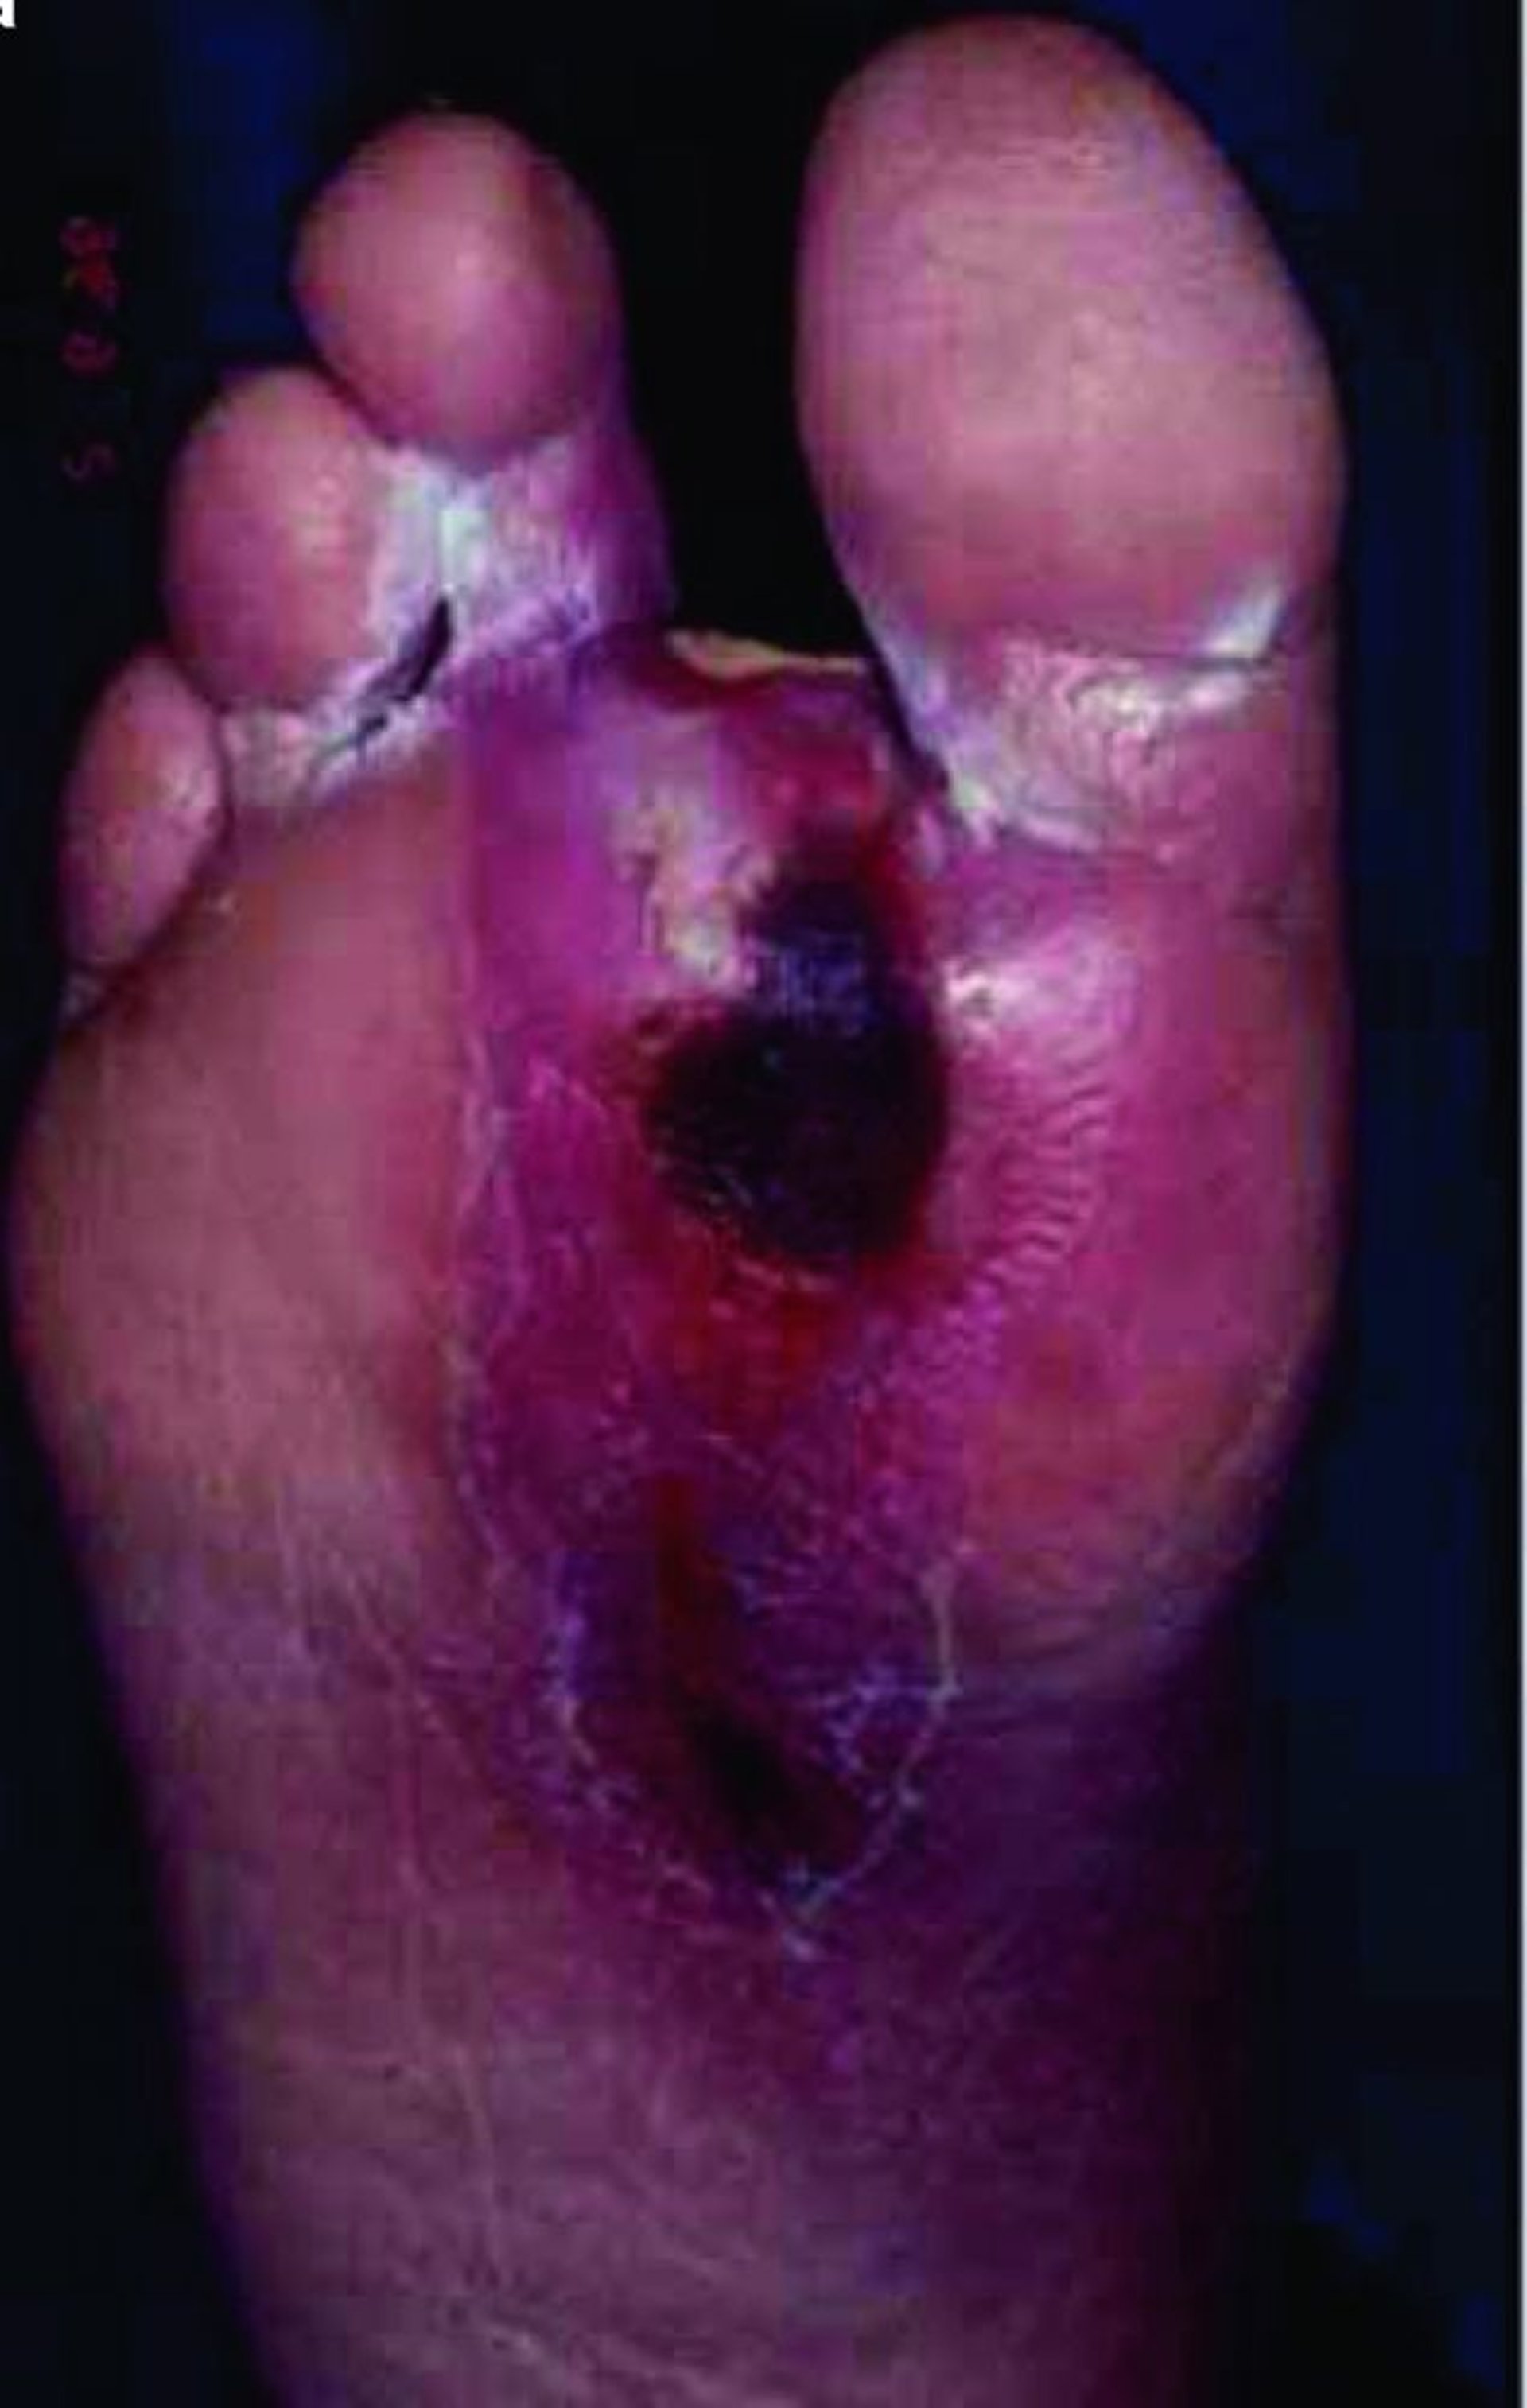

Foot Ulcer

Un paciente con diabetes a menudo desarrolla una enfermedad microvascular, que puede afectar la curación de la piel, por lo que incluso las roturas menores en la integridad de la piel pueden convertirse en úlceras más profundas y fácilmente infectarse, sobre todo en los miembros inferiores.